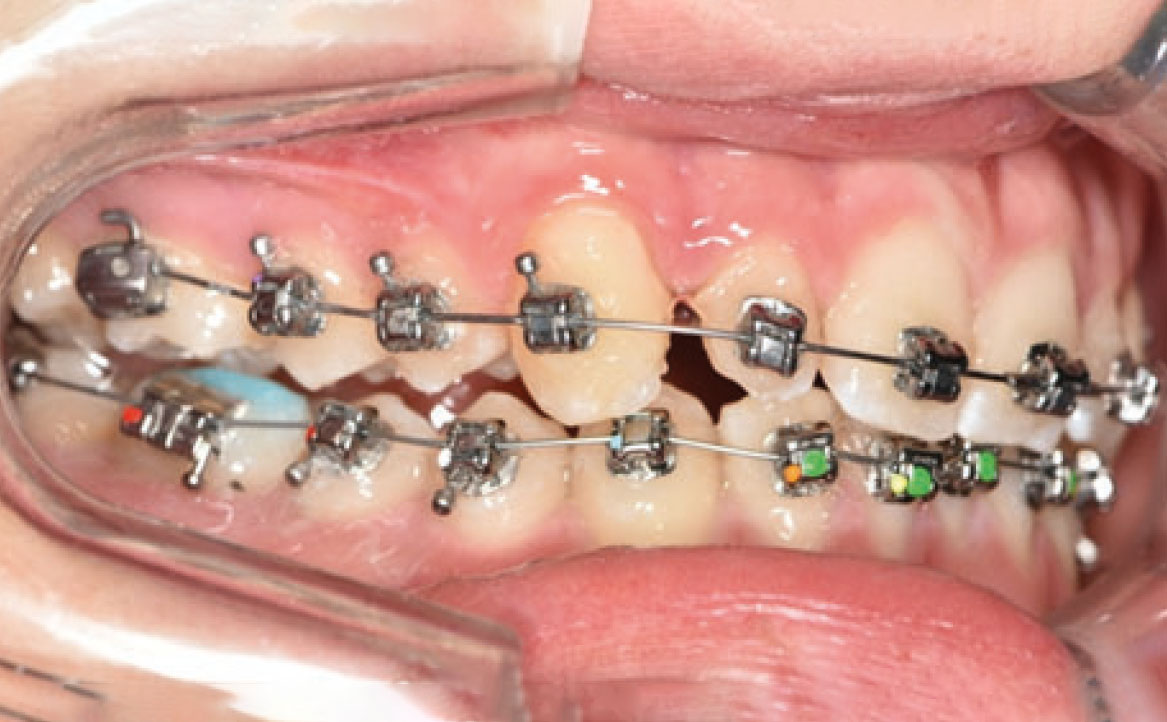

Nello specifico, sono stati eseguiti bandaggi superiori e inferiori con tecnica Damon per l’allineamento e il livellamento delle arcate dentarie con l’aggiunta di rialzi occlusali, al fine di aprire il morso, ed elastici di classe II a tempo pieno (fig. 5a-c).

Dopo circa dieci mesi, è stata eseguita la rimozione dei rialzi occlusali ed è stato ridotto il tempo di utilizzo degli elastici da 24 a 12 ore (solo nelle ore pomeridiane e notturne) (fig. 6a-d). Successivamente, il paziente ha chiesto anche di migliorare l’aspetto estetico degli elementi microdontici 12 e 22. Dopo una discussione con un collega, è stata proposta l’aggiunta di materiali compositi sul lato mesiale e distale di entrambi gli elementi. L’alternativa sarebbe stata l’uso di faccette in composito.